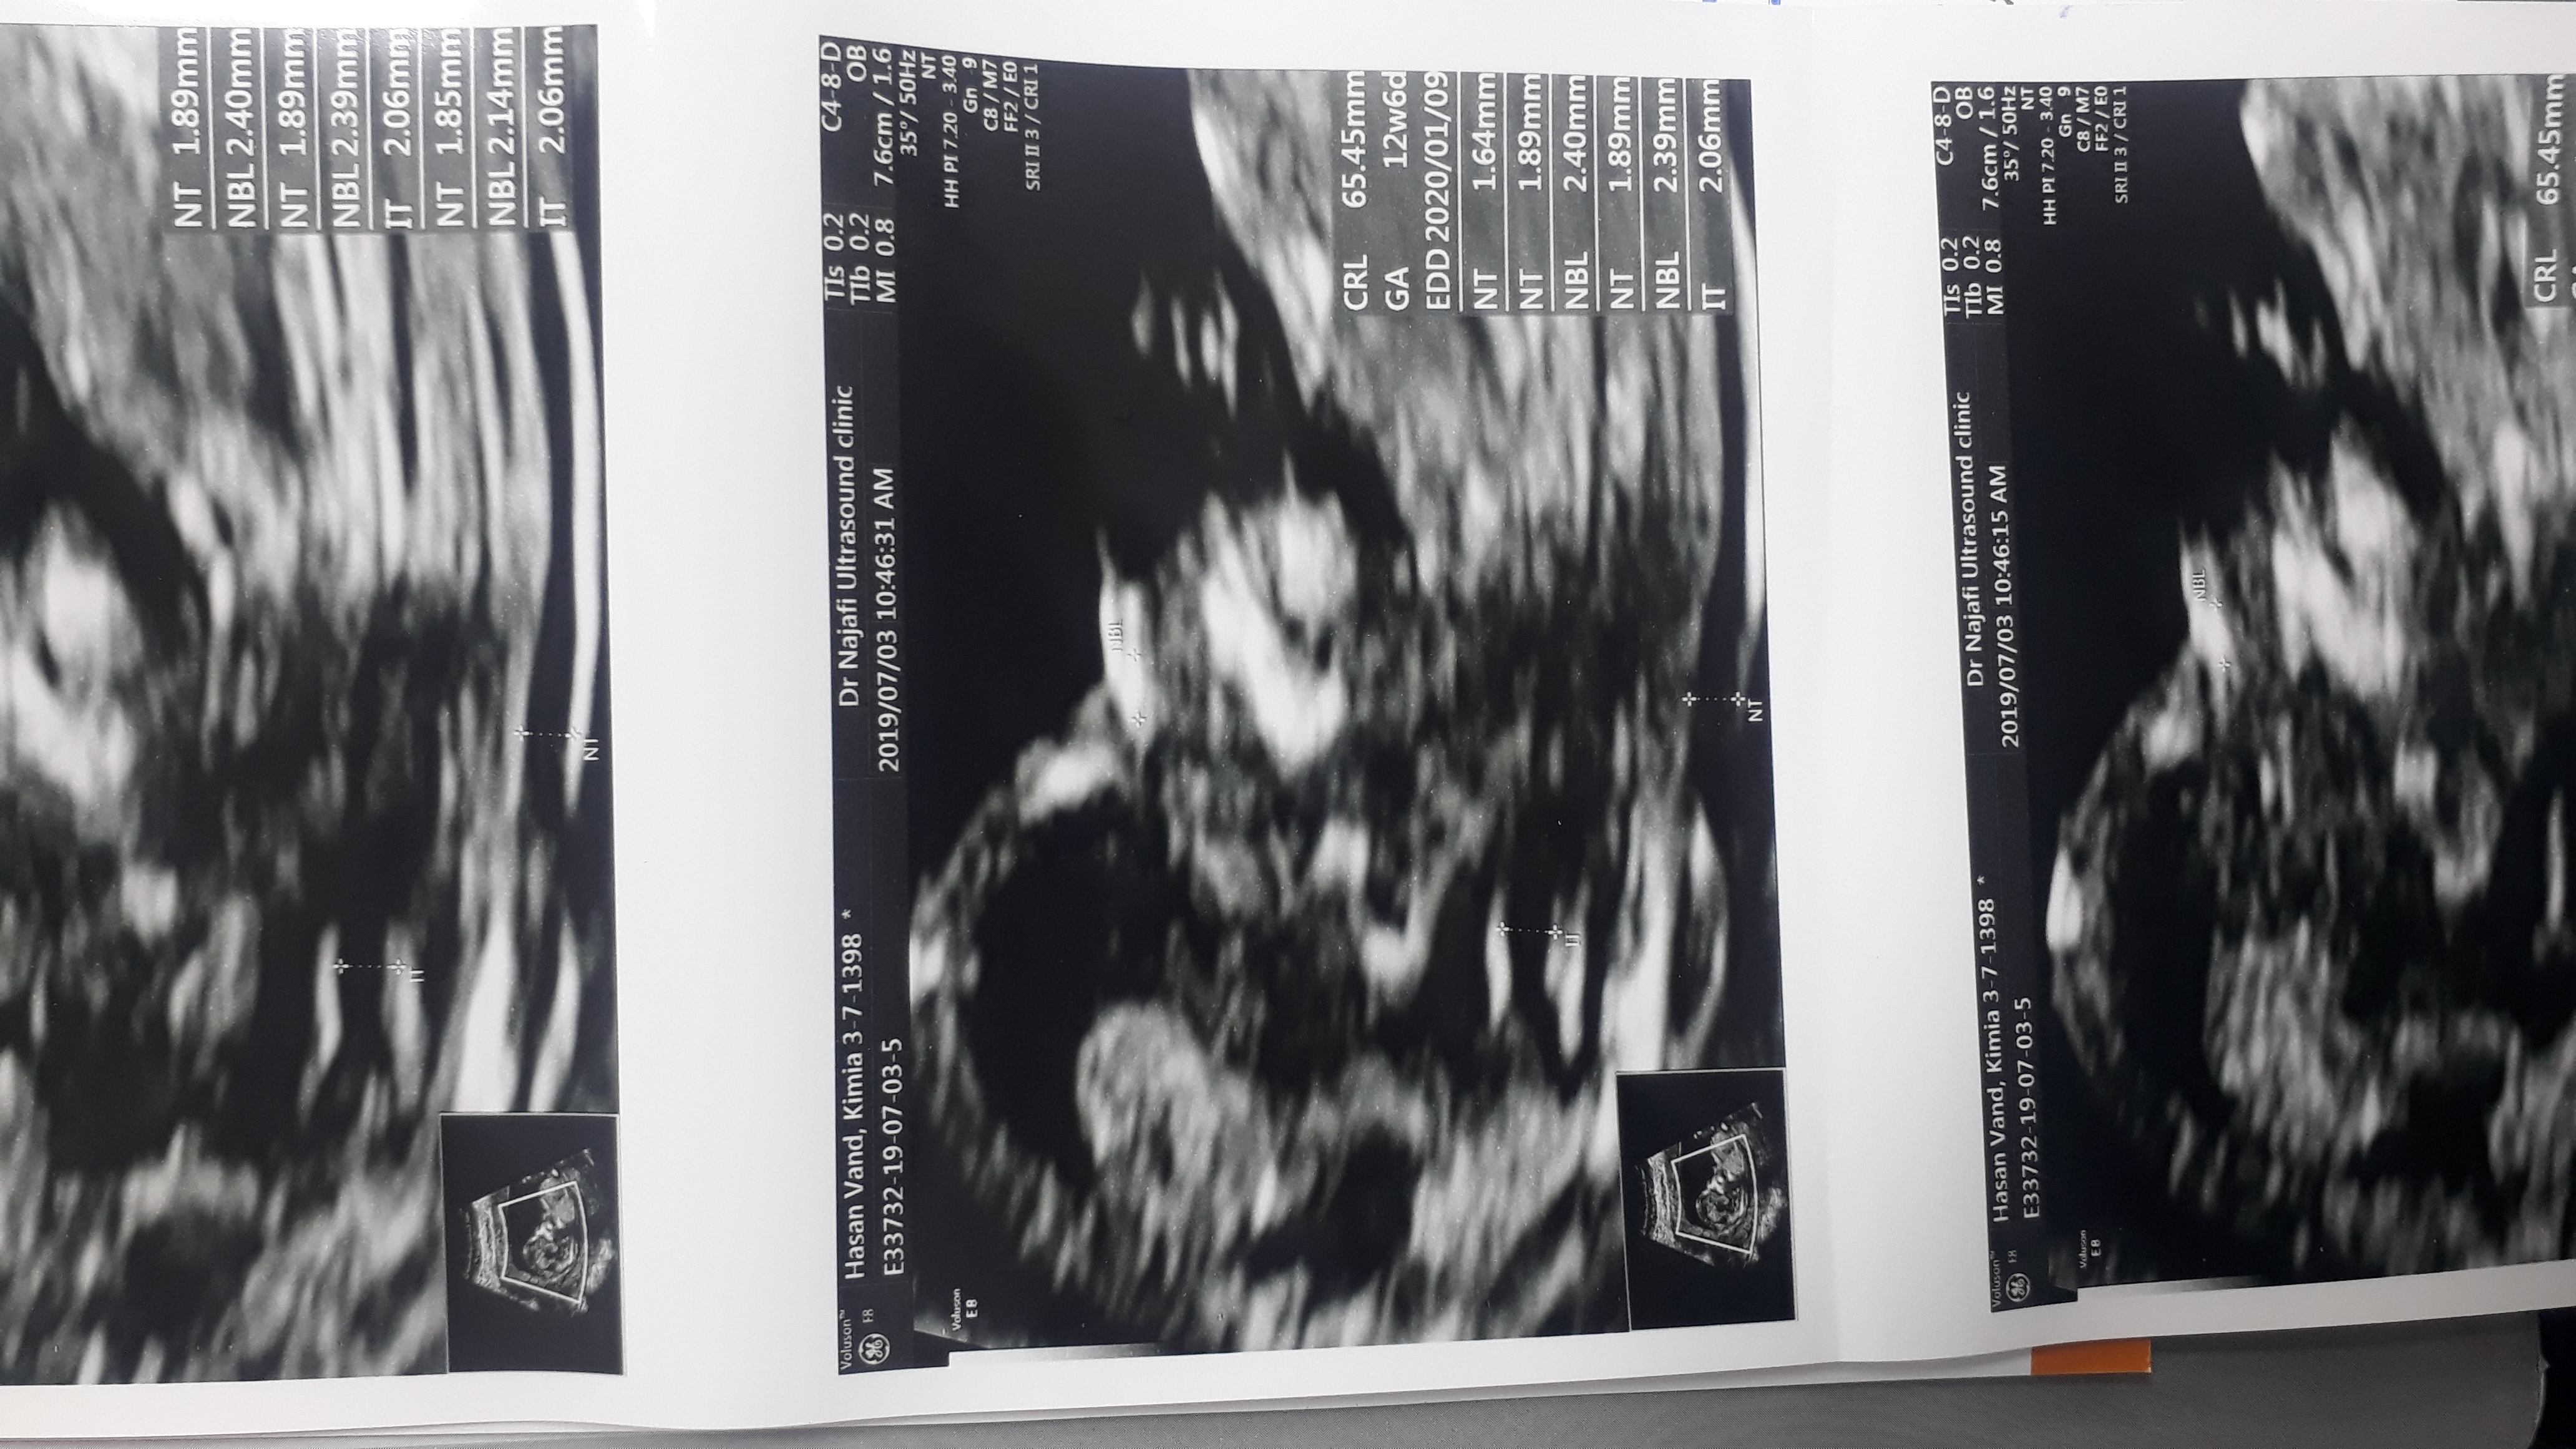

shahrzad74 مدیر عضویت: 1397/01/28 تعداد پست: 32018 عنوان سونوی ان تی | مشاهده متن کامل بحث + 894 بازدید | 137 پست برا شما NBرو هم نوشته؟من اصن حرفی درمورد تیغه بینی نزده فقط ان تی رو گفته مــن،دلم روشن است...خــدا هنوز دوستمــان دارد ♥️🙃 1398/07/17 | 17:10 0 نفر لایک کرده اند ... گزارش تاپیک نامناسب

shahrzad74 مدیر استارتر عضویت: 1397/01/28 تعداد پست: 32018 عزیزم از اون عکس سمت راستی از نزدیک و صاف بگیر واضح ببینم مــن،دلم روشن است...خــدا هنوز دوستمــان دارد ♥️🙃

afsaneh67 عضویت: 1398/06/20 تعداد پست: 13857 ازین لحاظ که تو برگه ننوشته 🤕 عکس برگه سونوتو بزار عزیزای دلم لطف میکنین برای سلامتی گل پسرم یه صلوات بفرستین؟اگه فرستادین بگین منم برای حاجت شما صلوات بفرستم مهربونا🤩😍😘